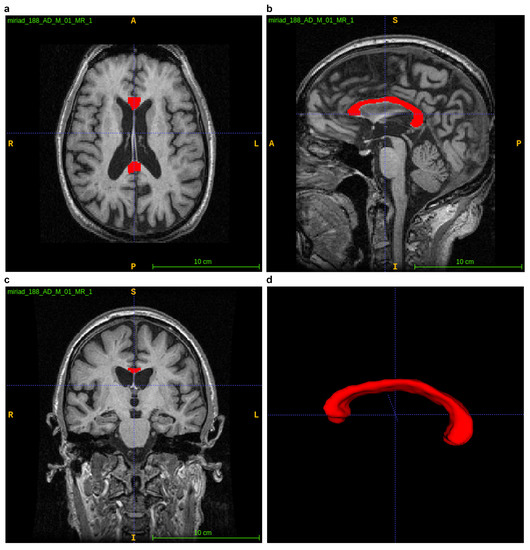

ITK–SNAP is an interactive open source software package established on ITK and designed for segmenting medical images, particularly segmenting 3D anatomical regions of interests. ITK–SNAP enables segmenting with the use of a user-friendly interface. The open source code can be utilised freely, so the group of its users is growing [18]. As shown in Figure 5, the orthogonal axial, sagittal and coronal planes are displayed on the user interface. It also allows the CC to be zoomed, paned and rotated using the visualisation tool, making it easier to evaluate the CC.

Figure 5. Using the ITK–SNAP platform to visualise the CC. (ac) displaying axial, sagittal and coronal planes; (d) 3D visualization of segmented CC.